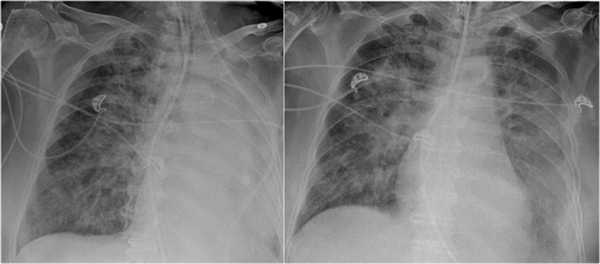

Ателектаз верхней доли правого легкого.

Оцените ниже лежащие изображения, а после продолжите чтение.

- Трехгранное затенение.

- Подъем правого корня легкого

- Облитерация загрудинного пространства (указано стрелкой).

На ПЭТ/КТ визуализируется опухоль легкого с обструкцией правого верхнедолевого бронха, как следствие ателектаз верхний доли правого легкого.

Также очень частым проявлением ателектаза является подъем диафрагмы, что хорошо визуализируется на ниже представленной рентгенограмме (указано синий стрелкой).

У данного пациента карцинома легкого с билатеральным метастазированием в легкие (указано красными стрелкам).